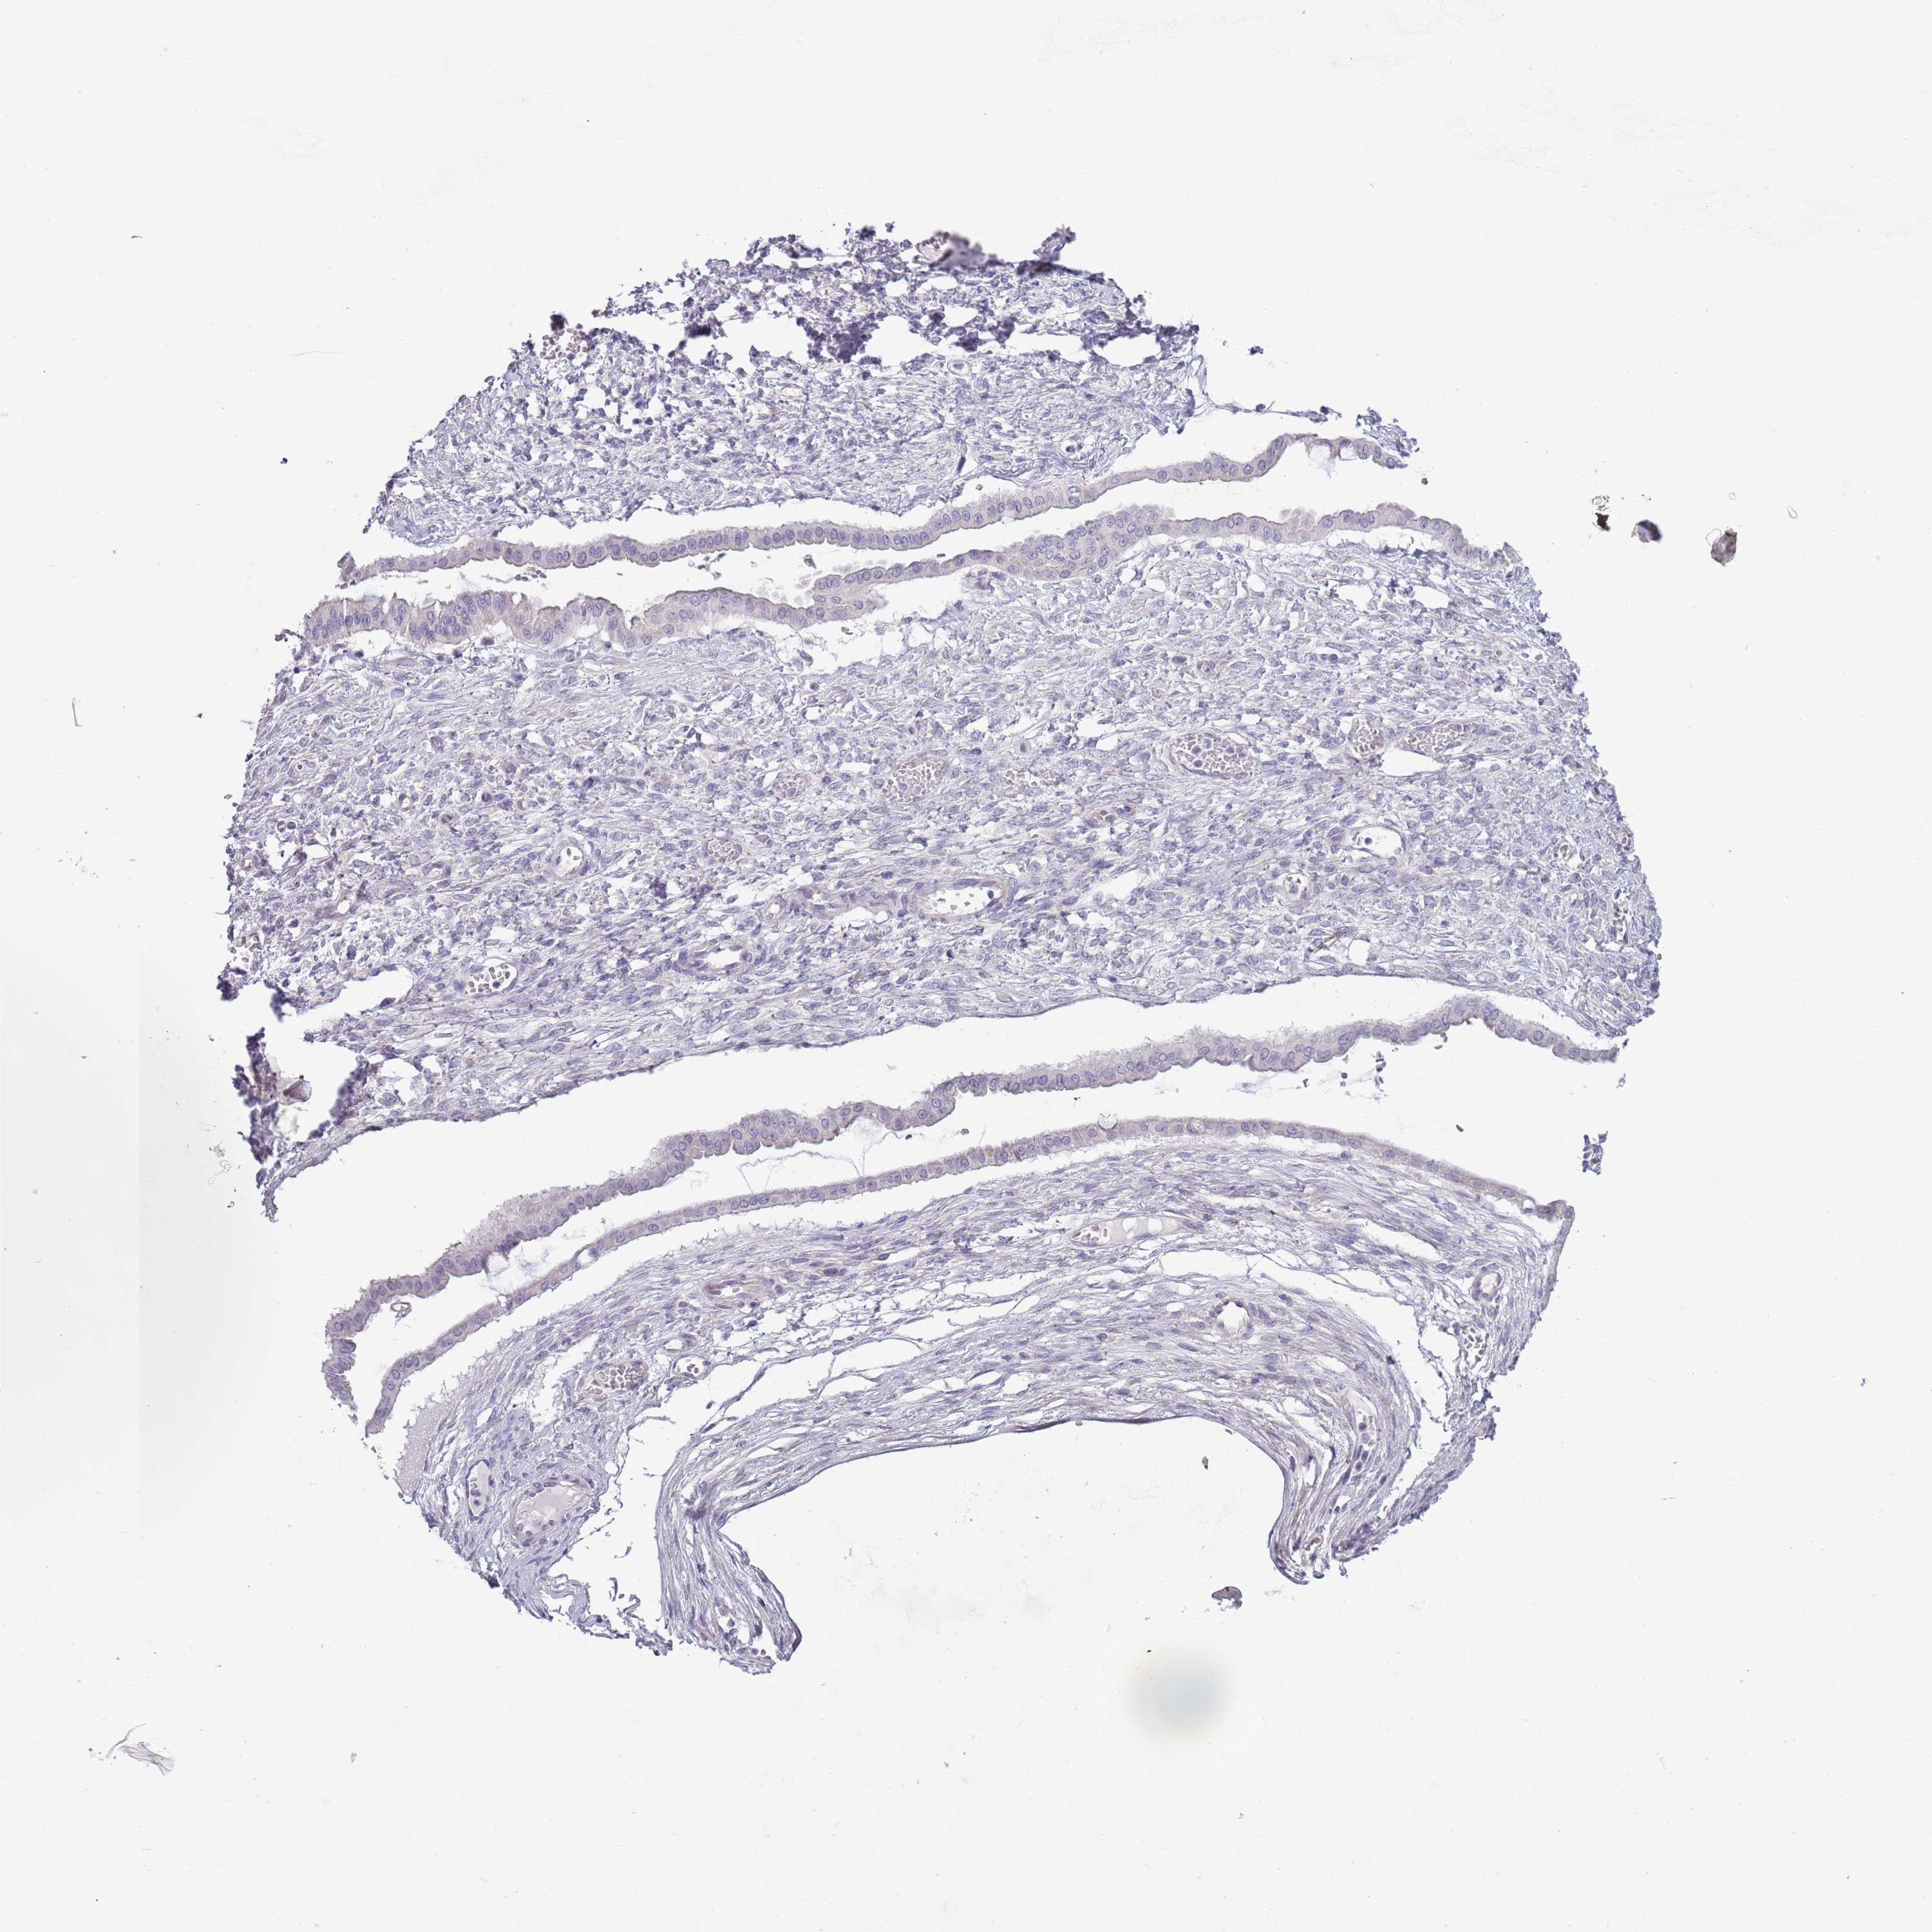

OVARIAN CANCER - Protein expressioni

A mouse-over function shows sample information and annotation data. Click on an image to view it in a full screen mode. Samples can be filtered based on level of antibody staining by selecting one or several of the following categories: high, medium, low and not detected. The assay and annotation is described here.

Note that samples used for immunohistochemistry by the Human Protein Atlas do not correspond to samples in the TCGA dataset.

Antibody stainingi

Antibody staining in the annotated cell types in the current human tissue is reported as not detected, low, medium, or high, based on conventional immunohistochemistry profiling in selected tissues. This score is based on the combination of the staining intensity and fraction of stained cells.

Each image is clickable and will lead to virtual microscopy that enables deeper exploration of all samples and also displays staining intensity scores, fraction scores and subcellular localization as well as patient and tissue information for each sample.

Antibody HPA048884

Cystadenocarcinoma, serous, NOS

Carcinoma, NOS

Cystadenocarcinoma, mucinous, NOS

Carcinoma, endometroid